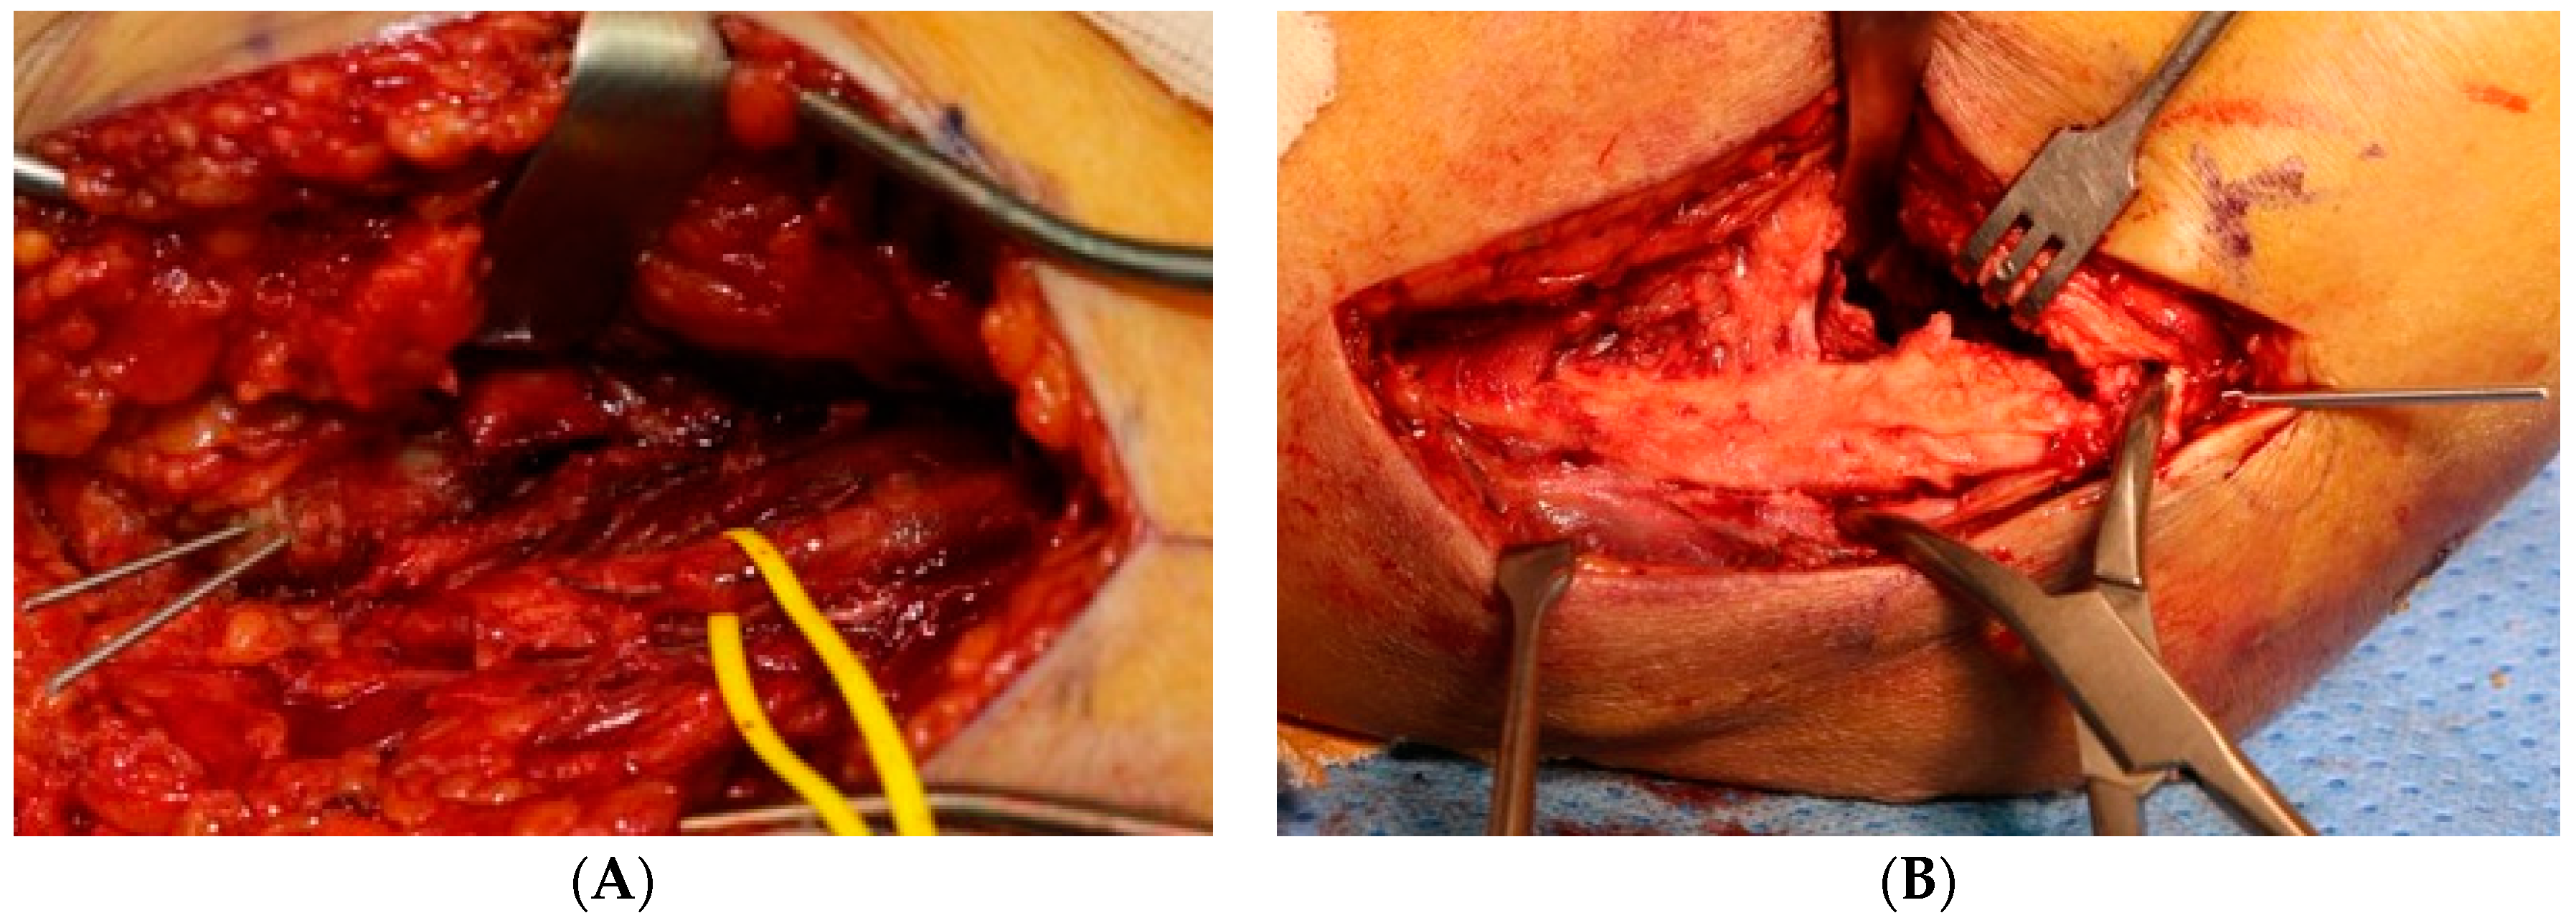

A multivariate logistic regression analysis showed that combined fracture operation (odds ratio 10.467; 95% CI 1.880–58.257; p = 0.007) and TBW (odds ratio 9.176; 95% CI 1.474–57.135; p = 0.018) were independent risk factors for non-union after ORIF in distal humerus fracture (Figure 3 and Table 5).

Figure 3.

A 67-year-old female patient with non-union after ORIF due to distal humerus fracture with usage of tension band wiring as the fixation method (A) pre-operative simple radiograph, (B) immediate post-operative simple radiograph, (C) a non-union was observed in the simple radiograph 7 months after the surgery.